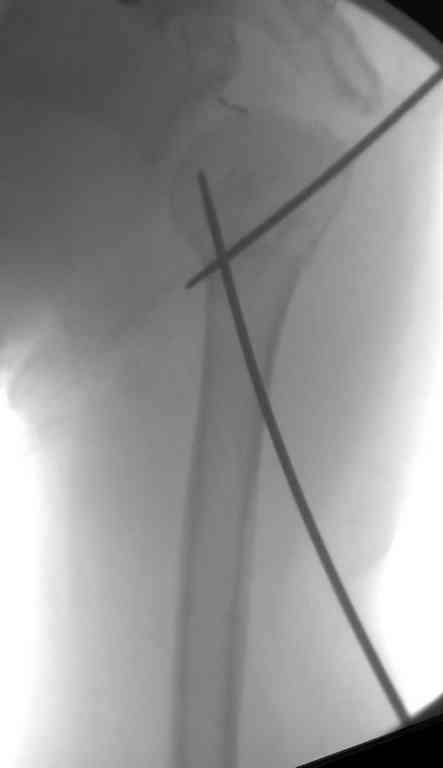

Сделали напряженными спицами по методике А.Ф.Лазарева со товарищи Репозиция сделана спицевым дистрактором, проксимальная спица была проведена в полскости деформации перпендикулярно оси наклонившейся головки. Получилось все довольно легко. Спицы малость покороче можно было сделать, ну да удалять потом легче будет.

Картинка в приложении.

Очень даже неплохо получилось. Молодцы! Лучше чем на 3D "репозиции".

Все заняло 1 час. Собственно введение фиксаторов - минут 20.

Оставили в косынке, сразу разрешены маятникообразные движения в плечевом суставе. Дальше по ходу расскажу.

В приложении. Схема простая - по спице в каждый отломок, полукольцо проксимально, кольцо дистально, два телескопа. Как уже писал, ключевым моментом было введение спицы в плоскости диформации проксимального

оттдела плеча.